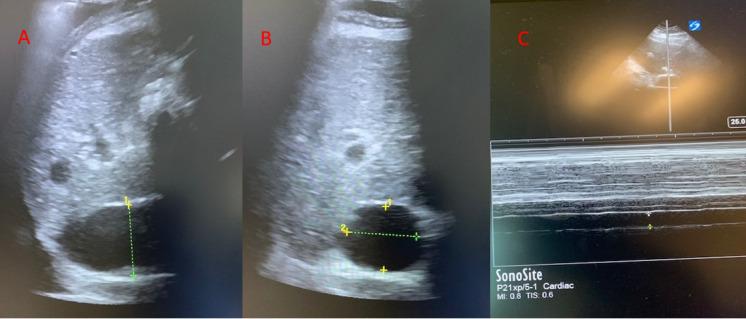

急性肾损伤(AKI)对于入住重症监护病房(ICU)的患者而言是一个重大问题,这是由于其发病率高且伴有死亡率,需要肾脏替代治疗(RRT)的AKI发生率超过5%,而AKI的死亡率超过60%[1,2]。超声可用于识别有AKI风险的患者并辅助进行AKI管理。ICU中AKI的危险因素不仅包括低灌注,还包括静脉淤血和容量超负荷。容量超负荷和血管淤血与多器官功能障碍及更差的肾脏预后相关。每日及总体液体平衡、每日体重以及水肿的体格检查可能不准确,且会掩盖真正的全身静脉压[3,4,5]。床旁超声可让医护人员评估血管血流模式,并对容量状态进行更可靠的评估,以指导并个体化治疗。超声检查的心脏、肺部和血管模式可识别前负荷反应性,应评估前负荷反应性以安全地管理正在进行的液体复苏,并评估液体不耐受的迹象。在此,我们概述了床旁超声的应用,特别强调以肾脏为中心的策略,即在识别肾损伤类型、评估肾血管血流、静态测量容量状态以及对危重症患者进行容量优化的动态评估方面的应用。